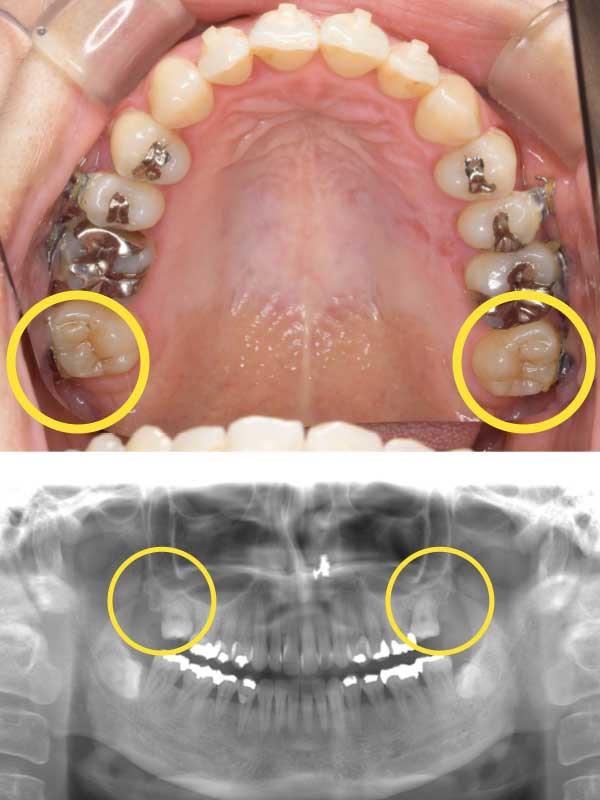

こちらの患者様は、すでに奥歯を抜歯しており、「噛む機能を回復するにはインプラントしかない」と宣告されていました。

しかし、「手術が怖い」「体に人工物を入れることに抵抗がある」という強い思いから、インプラント以外の方法を模索して当院へお越しになりました。

実は、親知らずは、矯正治療で移動させれば、欠損した奥歯として再利用できます!

通常、歯を失った場所にはインプラントやブリッジを検討しますが、当院では「親知らずを矯正装置で奥に移動させ、抜けた奥歯のスペースを埋める」という治療を行いました。

不要だと思われがちな親知らずを、失った奥歯の「代役」として再配置する、非常に合理的で身体に優しい方法です。

ご自身の天然歯をそのまま移動させるため、人工物を埋め込む手術の必要がありません。100%自分の歯で、違和感のない自然な噛み心地を取り戻せます。 - 痩せた骨まで「自然に再生」

歯を抜いて時間が経つと骨は痩せてしまいますが、矯正で歯をゆっくり動かすと、周囲の骨や歯ぐきも一緒に引き寄せられて再生されます。これはインプラントにはない、天然歯だけの力です。 - 一生涯の健康リスクを抑える